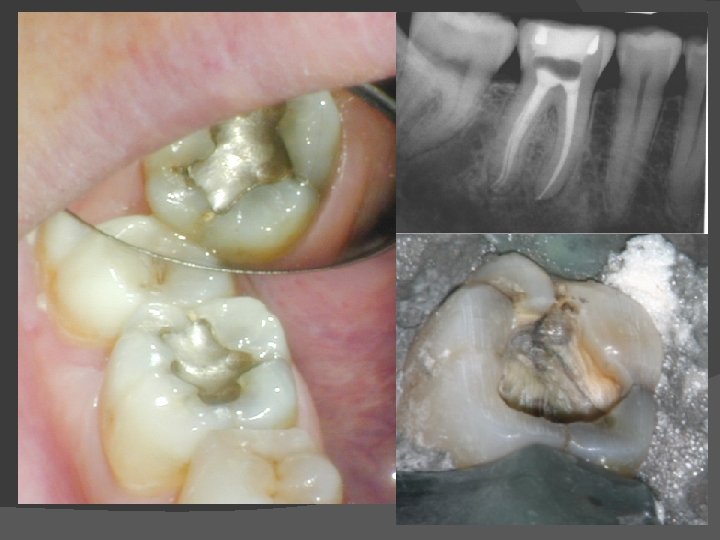

Endodontic Pretreatment – Why? 1. To facilitate placement of rubber dam 2. To allow proper access cavity form 3. Prevent leakage of saliva into access during treatment 4. Prevents cusp fracture ( loss of landmarks) between appointments. ALL BANDS MUST BE CEMENTED 5. Prevent recontamination of canals and leakage of medicaments between appointments 6. To make room for placement of medicaments Wednesday, March 3, 2021 Fac. of Dentistry, Univ. MB, WHC copywrite

Pre. Tx - Anterior teeth No Endodontic treatment can proceed without marginal seal � ALL caries must be removed before entering pulp space � Defective & suspect restorations should be replaced with IRM or restorative filling. � Wednesday, March 3, 2021 Fac. of Dentistry, Univ. MB, WHC copywrite

Pre. Tx - Posterior teeth First requirement is a stable clamp � Large IRM or composite filling may add seal to chamber � Chamber should be located & protected before restoration � Copper band or Ortho band may have to be cemented for seal � Wednesday, March 3, 2021 Fac. of Dentistry, Univ. MB, WHC copywrite

Copper Band pretreatment Depends upon remaining tooth enamel � Remove all caries and unsupported enamel � Assess stability of clamp and marginal seal � Locate pulp chamber, protect with small cotton pellet & layer of Cavit � Wednesday, March 3, 2021 Fac. of Dentistry, Univ. MB, WHC copywrite

Copper Band pretreatment Contour correct size copper band � Contour & crimp for 1 mm+ gingival margin � Dry crown & enamel with air syringe � Cement band with Polycarboxylate cement & stabilize until fully set. � Polish and check for sharp edges � Wednesday, March 3, 2021 Fac. of Dentistry, Univ. MB, WHC copywrite

Copper Band pretreatment Place IRM in central portion of band to rebuild crown shape � Reduce any projecting enamel cusps � Check occlusion with rubber dam off � Normal access can be made through occlusal � Wednesday, March 3, 2021 Fac. of Dentistry, Univ. MB, WHC copywrite

Copper Band pretreatment Band should NOT have overhanging margins � 1 -2 mm cement layer necessary to replace missing coronal substance � Saliva must NOT leak under margin � Perio irritant develops � Wednesday, March 3, 2021 Fac. of Dentistry, Univ. MB, WHC copywrite

Copper Band errors Band MUST be cemented to crown � Contouring and sizing very important � Never remove band between appointments � Crown should be restored with more permanent restoration as soon as Tx done. � Wednesday, March 3, 2021 Fac. of Dentistry, Univ. MB, WHC copywrite

S. S. (Ortho) Band pretreatment Ortho SS band may fit some cases if margin level � When cemented, normal clamp should be stable � Band should not move or impinge on gingival tissues � Sometimes, gingival soft tissue contouring may be needed before pretreatment � Wednesday, March 3, 2021 Fac. of Dentistry, Univ. MB, WHC copywrite